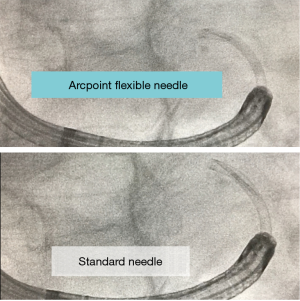

Similarly, Medtronic has introduced the flexible ArcpointTM pulmonary needle. This is also designed to maintain longitudinal stability while providing substantive flexibility and limited displacement of their variably curved EdgeTM catheters used during ENB. The needle is available in two sizes, 21 G and 18 G. Similar to the Olympus needle, it can be used with or without a style to adjust flexibility. The needle itself is 8 mm in length and attached to a braided and tapered sheath. When compared to traditional non-flexible aspirating needles, the ArcpiontTM needle would appear to be able to maintain its position with significantly less catheter displacement (Figure 3). Given the recent introduction in both tools, there is limited human data as of yet with respect to performance, yield, etc. (16).